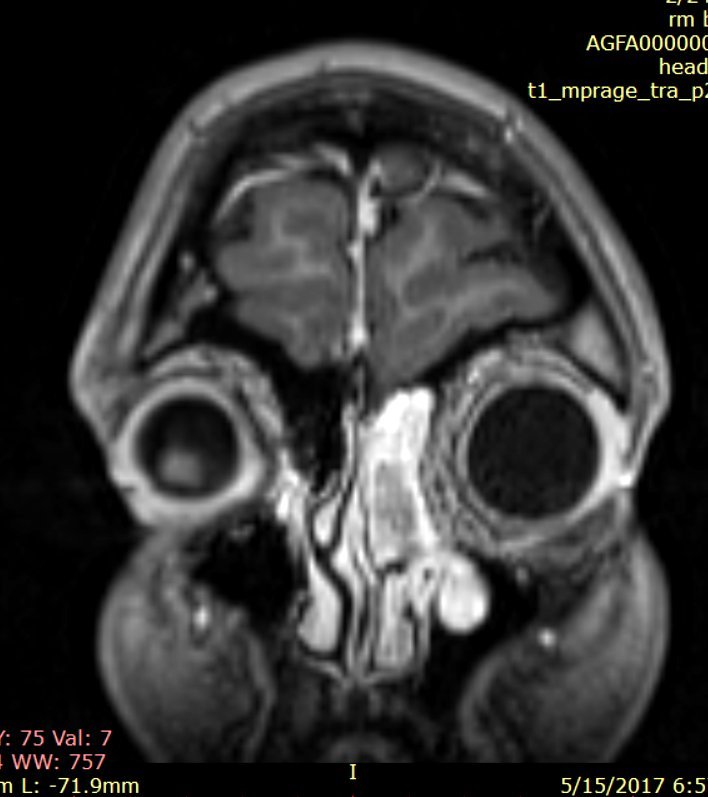

Examenul pentru reevaluare endocrinologică (Doamna Dr. Simona Jercălău – Brain Institute, Spitalul Monza) ridică suspiciunea unei secreţii ectopice paraneoplazice de ADH, contrazicând astfel diagnosticul de SIADH stabilit în urmă cu 5 ani. Coroborarea cu diagnosticul ORL, cu examenele imagistice şi cu literatura de specialitate (20 de cazuri descrise în lume până în anul 2014) stabilesc diagnosticul prezumptiv de estezioneuroblastom etmoidal stâng extins fronto-maxilar secretant de vasopresină (stadializare Kadish – grup b) şi se decide efectuarea intervenţiei chirurgicale endoscopice transnazale în scop diagnostic şi curativ (fig. 2).

Fig.2: Examen RMN craniocerebral cu substanță de contrrast efectuat preoperator